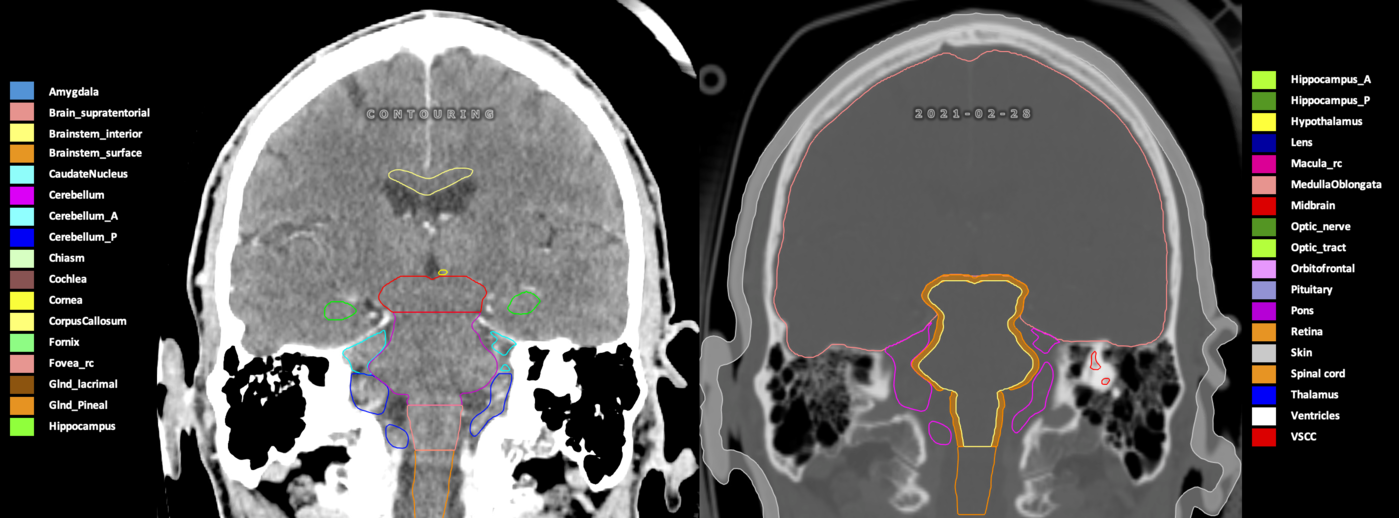

Eekers et al. have published an international neurological atlas for contouring of organs at risk in consensus with the European Particle Therapy Network (EPTN) in 2018 and an update in 2021. The purpose of this consensus atlas is to decrease inter- and intra-observer variability in delineating OARs relevant for neuro-oncology.

Included are all OARs known to be relevant for radiation-induced toxicity in neuro-oncology: brain, brainstem (midbrain, pons, medulla oblongata), chiasm, cerebellum (anterior & posterior), cochlea, cornea, hippocampus (anterior & posterior), hypothalamus, lens, lacrimal gland, optic nerve, pituitary, skin, and vestibular & semicircular canals. To further facilitate research on cognition, vision and radiological changes after irradiation of the brain, potential clinically-relevant OARs are included: amygdala, caudate nucleus, cerebellum (anterior & posterior), corpus callosum, fornix, macula, optic tract, orbitofrontal cortex, periventricular space (PVS), pineal gland, and thalamus.

Three-dimensional delineation of the 25 consensus OARs for neuro-oncology are shown on CT (WW/WL 120/40, 3000/600), 3T MR images, (T1Gd, T2FLAIR 1mm) and 7T MR (MP2RAGE 0.7 mm). All are presented in transversal, sagittal and coronal view.